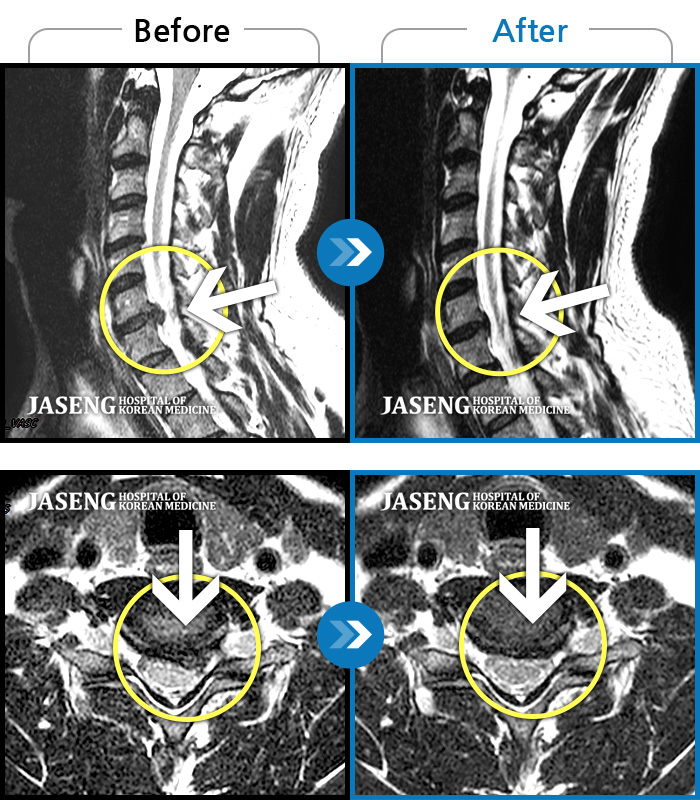

목디스크

강남 · 강만호 원장

양측 승모근 통증과 목 통증, 견갑골 통증으로 고개를 돌릴때 통증을 호소하는 환자였습니다.

촬영시기

2019.11.18 ~ 2024.07.30

2024.08.09

조회수 480